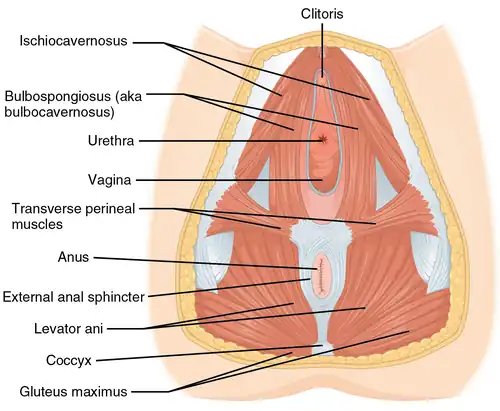

Muscles of the female perineum | |